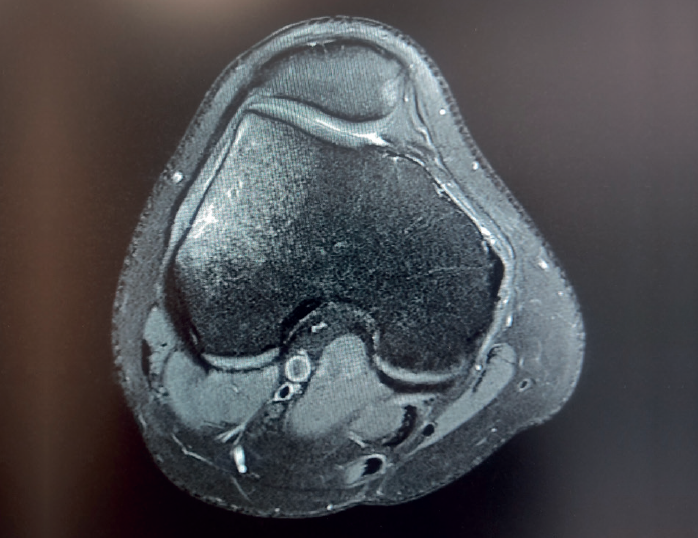

La RM es la prueba de imagen de elección para su diagnóstico, en la cual se muestra como una lesión de bordes mal definidos, que sobrepasa las cicatrices fisarias y que puede extenderse a las partes blandas adyacentes, con señal hipointensa en las secuencias potenciadas en T1 e hiperintensa en las secuencias T2, con supresión grasa y STIR (short tau inversion recovery)(6). Además, la imagen de RM puede revelar la presencia de fracturas trabeculares por impactación del hueso subcondral y hundimiento del cartílago suprayacente, que se presentan como líneas hipointensas en T2, paralelas a la superficie articular. Las lesiones por NAV presentan un patrón típico en la imagen de RM, con un borde serpenteado y presencia de doble contorno hiperintenso e hipointenso en las secuencias T2 (Figura 11).

retla.05210.fs2208018-figura11.png

Figura 11. Resonancia magnética de rodilla, que presenta luxación femorotibial inveterada, de 7 meses de evolución, en la que se aprecian focos de osteonecrosis avascular, con bordes serpenteados e intenso edema óseo circundante. A: corte coronal, secuencia T2; B: corte sagital, secuencia T1; C: corte axial, secuencia con supresión grasa.